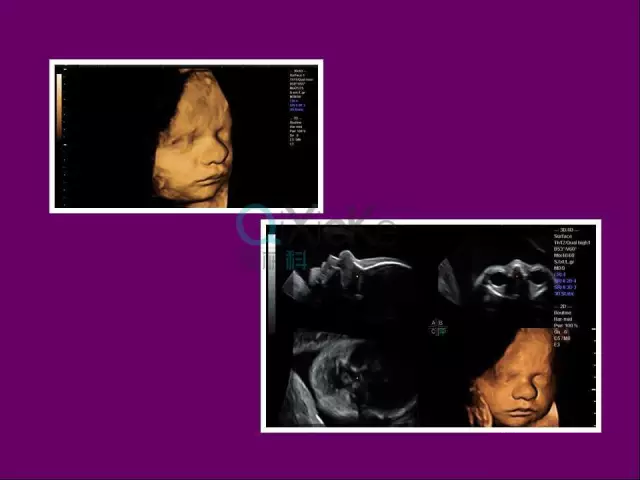

ge彩超s8怎么样中山市宝元医院引进GE Voluson S8 实时四维高端智能彩超_https://www.jmylbn.com_新闻资讯_第1张

超高清立体成像:通过先进的容积探头和算法,清晰呈现胎儿面部、肢体及内脏结构,图像分辨率显著提升,微小细节一目了然。

动态四维影像:实时捕捉胎儿微笑、哈欠、握拳等生动画面,让准爸妈提前与宝宝“见面”,增强孕期互动体验。